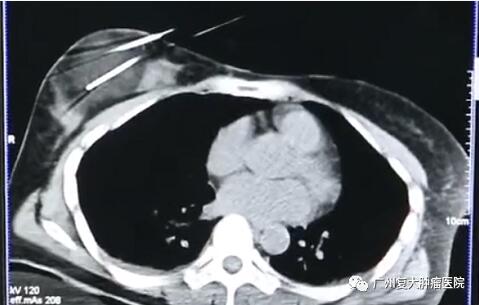

影像結(jié)果顯示

來自印尼Mary曾因左乳的小結(jié)塊去當?shù)蒯t(yī)院檢查發(fā)現(xiàn)自己患上乳腺癌。為了免受傳統(tǒng)手術(shù)開刀之“苦”,Mary來到我院就診。入院后檢查發(fā)現(xiàn)Mary的乳腺癌組織直徑已從2.2cm擴大至6cm,專家團隊經(jīng)過會診最終確認了其治療方案——冷凍消融治療。

超聲引導下將探針插入腫瘤區(qū)內(nèi),當溫度下降超過一定水平時,冰晶開始在腫瘤細胞內(nèi)部形成,凍結(jié)供應營養(yǎng)的血管,停止運輸養(yǎng)分,摧毀腫瘤細胞組織。持續(xù)幾分鐘后,迅速又復溫。經(jīng)過這樣兩個循環(huán)后,腫瘤病灶完全被“凍結(jié)”,進而達到治療效果。由于病灶位置淺,離皮膚較近,因此在術(shù)中還要對皮膚采取保護措施,以免凍傷皮膚。

3天后Mary就恢復日常活動能力,術(shù)后半年她體內(nèi)的腫瘤指標已下降到正常范圍了。10年來,Mary的健康情況良好,復查顯示腫瘤現(xiàn)在僅剩一個疤痕。